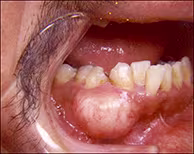

A 38-year-old male presented with a slowly growing mass of the right mandible. The lesion displaced the mandibular canine and premolar teeth on the same side.